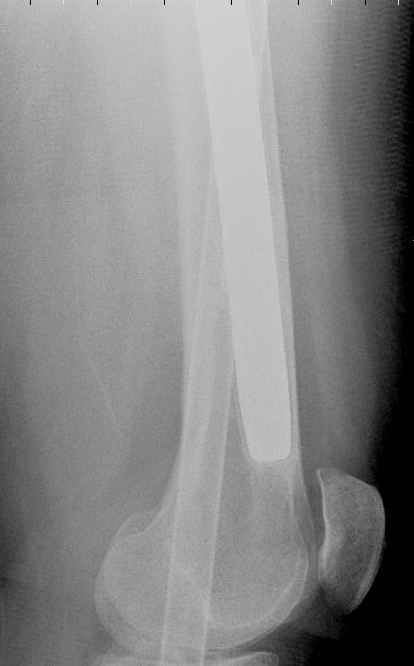

May I have some advice on the following case? Middle aged woman, No chronic medical problems, +tobacco use - but she promises she's going to quit! Original MVC in late 1990's, initial rod failed, and 2 subsequent exchanges failed (most recently shown in attached jpgs.)

Most recent one (6/2002) was apparently an open nailing to remove last broken nail, but no grafting was performed in conjunction. Now sent to me with broken 14mm R/T nail in place.WBC, Hgb, Chemistries normal.ESR 34CRP 4.2No other apparent locus of infection.I was considering a staged approach - removing nail and screws and obtaining cultures.If negative, proceed with exchange nailing with open grafting +/- BMP, But how best to deal with that pedestal distally and avoid anterior breech near patella? If positive cultures, what would be best option?Thanks. Tom Schaller Kalamazoo, MI.

In my opinion, there is no nail strong enough to tolerate a varus deformity of femur after nailing. The AP view of the distal femur shows that the femur has been repeatedly nailed in varus. The tip of the nail is short and lateral in distal lateral metaphysis. It should be central over the intercondylar notch and buried in the distal epiphyseal scar. This has resulted in constant bending forces on the nail (see the "windshield wiper" sign) and its eventual fatigue failure.

I would first determine the degree of varus deformity with a long standing AP x-ray. After nail removal, irrigation, debridement and reaming of the nonunion, specimens would be sent for pathology and culture. If there was any sign of infection, placement of custom made antibiotic nail e.g.

for two or three weeks would be performed before an ORIF plate fixation with Judet decortications and bone graft.

My first definitive treatment choice would be a long lateral tension band plate with insertion of proximal screws directed proximally at an angle of about 25-30 degrees. Correction of the varus would be accomplished by using a tensioning device distally or compressing with two eccentrically placed distal screws simultaneously as shown in Lawrence Webb's OTA BFC lecture

or two distal screws directed distally. Fixation would be completed by a pair of locking screws each side of the nonunion..

My second choice would be an Ilizarov compression over nail if there is familiarity with both nailing and Ilizarov technique.